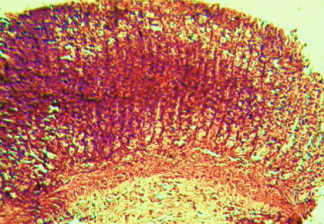

Histological evaluation of gastric lesion

Histological observation showed extensive damage of the gastric mucosa in the ulcer negative control group with necrotic lesions penetrating deeply into the mucosa accompanied by extensive edema and leucocyte infiltration of the submucosal layer (group 2).

Rats that received treatment with aqueous and methanol extracts of the leaves of D. thollonii had comparatively better protection of the gastric mucosa as seen by the reduction of ulcer area, reduced submucosal edema and leucocytes infiltration after 14 days of treatment (fig. 4).

Fig. 4: Histological study of acetic acid-induced gastric damage in rats

In fig. 4: (a’): histological section of a normal control rat: no injuries to the gastric mucosa are seen and the gastric wall is normal. ((b’): histological section of an ulcer negative control rat: there is severe destruction of the surface epithelium and necrotic lesions penetrating deeply into mucosa and submucosa layer. (c’): histological section of rats treated with Maalox (50 mg/kg): the gastric wall appears normally, but there is edema of mucosa and sub mucosa layer.(d’): the histological section of rats treated with Ranitidine (50 mg/kg): the gastric wall appears normally with all layers. (e’): the histological section of rats treated with 125 mg/kg of aqueous extract: there is mild disruption of the sub mucosal layer. (f’): histological section of rats treated with 250 mg/kg aqueous extract: there is moderate disruption of the surface epithelium. (g’): histological section of rats treated with 500 mg/kg of aqueous extract: there is mild disruption of the sub mucosal layer and edema of the muscle. (h’): histological section of rats treated with 125 mg/kg of methanol extracts: there is mild disruption of the epithelium surface and the sub mucosal layer and edema of the serosal layer. (i’): histological section of rats treated with 250 mg/kg of methanol extract: there is mild disruption of the epithelium surface and edema of the submucosal and serosal layers. (j’): histological section of rats treated with 500 mg/kg of methanol extract: there is moderate disruption of the epithelial surface although the gastric wall appears normally.